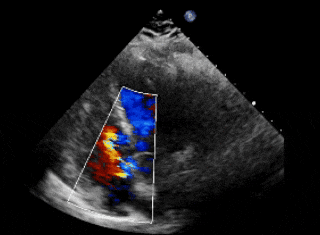

右盘面展开后

前推钢缆使其成型

超声下可见双盘面骑跨

锁定后评估

封堵器形态良好,基本无残余分流